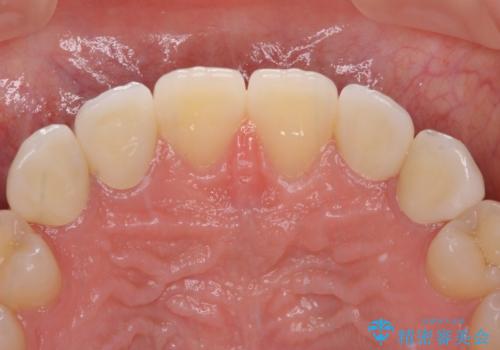

前歯の奇形歯 オールセラミッククラウンによる審美歯科治療

正中の隙間は矯正治療により閉じ、左右の4歯はオールセラミッククラウンにて補綴することとしました。

前歯2本もセラミッククラウンを装着することで隙間を閉じる治療方法もあるかと思いますが、健全な歯を削る必要は全くなく、矯正治療で対応することが望ましい治療であると考えます。